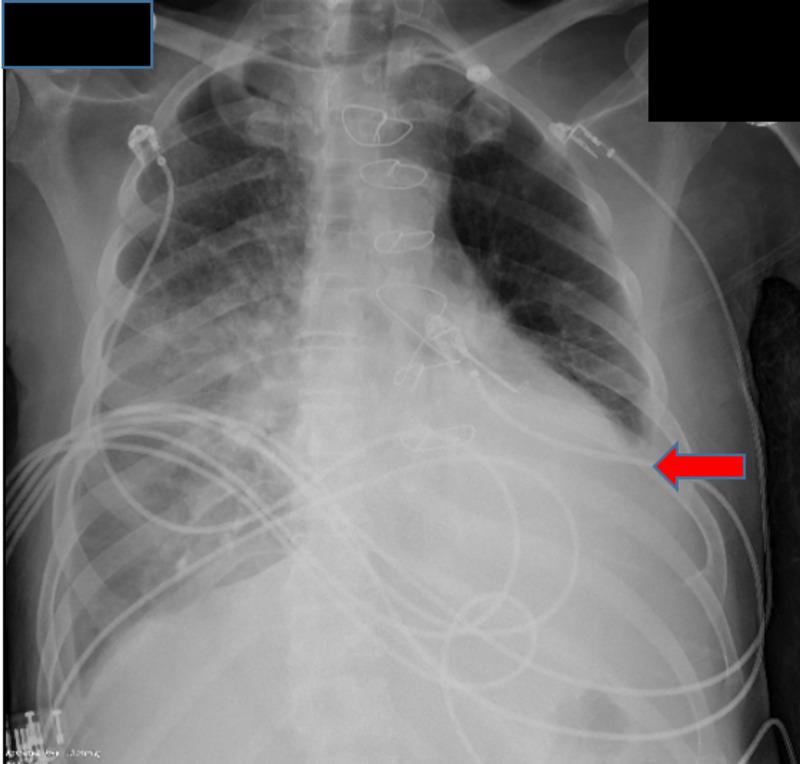

二尖瓣置换术后瓣周漏的复杂病例

A Complicated Case of a Paravalvular Leak Following Mitral Valve Replacement.

Paravalvular leaks (PVL) are an uncommon sequelae of valve replacement but can be seen as a complication of both mechanic and prosthetic valves. Patients with PVL may remain asymptomatic or have detrimental complications, which include heart failure, hemodynamically significant hemolysis, and endocarditis. Management depends on the clinical presentation and the degree of the valvular leak. We hereby present a case report of a patient with a complicated clinical course secondary to a PVL of the mitral valve. The patient had a recent mitral valve replacement and presented with symptoms of heart failure that was refractory to standard medical therapy. Valvular abnormality was not seen with initial trans-thoracic echocardiogram (TTE), but with high clinical suspicion, a trans-esophageal echocardiogram (TEE) was done confirming a PVL. The patient's condition continued to deteriorate; he became hemodynamically unstable with end-organ damage. Cardiothoracic surgery was consulted for surgical repair of the PVL. The patient, however, remained too unstable for surgery and the family opted for comfort measures per the patient's wishes.

摘要

瓣周漏(PVL)是瓣膜置换术后不常见的后遗症,但可视为机械瓣膜和人工瓣膜的并发症。瓣周漏患者可能无症状或出现有害并发症,包括心力衰竭、具有血流动力学意义的溶血和心内膜炎。治疗取决于临床表现和瓣膜漏的程度。我们在此报告一例二尖瓣瓣周漏继发复杂临床过程的病例。该患者近期进行了二尖瓣置换术,出现了标准药物治疗无效的心力衰竭症状。最初的经胸超声心动图(TTE)未发现瓣膜异常,但由于临床高度怀疑,进行了经食管超声心动图(TEE)检查,证实存在瓣周漏。患者病情持续恶化;他出现血流动力学不稳定并伴有终末器官损害。咨询心胸外科进行瓣周漏的手术修复。然而,患者仍因过于不稳定而无法进行手术,家属根据患者意愿选择了姑息治疗措施。